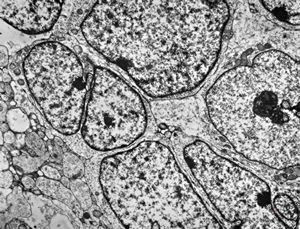

M,55y. | meningotheliomatous meningeoma

F,75y. | meningotheliomatous meningeoma